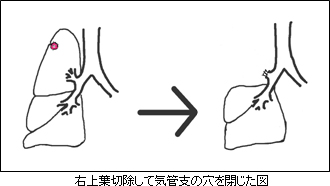

上の図は右上葉の肺がんに対して右上葉切除術を施行したところですが、気管支の穴は自動縫合器(金属のホッチキス:ステープラー)で閉じます。肺を取ったあとの空間は、残りの肺が少し膨らむのと、横隔膜があがって残りの肺全体が膨らみ移動してその空間を埋めます。